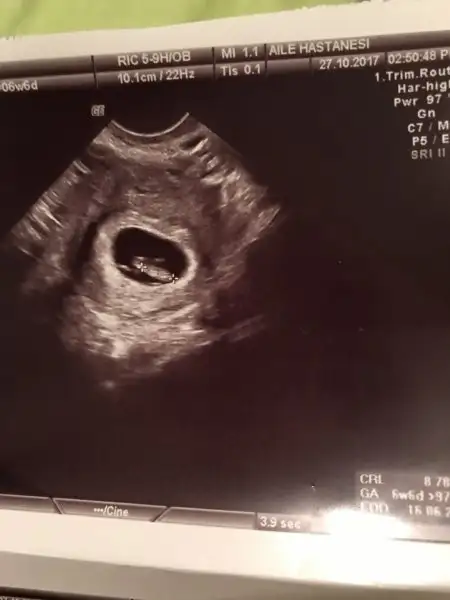

Daha bebek olusmamistir senin.Canım 7 haftalık olsun ancak yorum yapılabilir.8 hafta olsa olmaz mesela çünkü bebek hareket ediyor rahim içinde yer değiştirebiliyor.Canım benim kesede tam ortada görünüyor. Yeni olduğu için galiba di mi

Tamam canım beklicez artık, Allah gönlümüzden geçeni nasip etsin inşallahDaha bebek olusmamistir senin.Canım 7 haftalık olsun ancak yorum yapılabilir.8 hafta olsa olmaz mesela çünkü bebek hareket ediyor rahim içinde yer değiştirebiliyor.

Canım kese yorumu için 7 haftalık ultrason görüntüsü lazımEki Görüntüle 2068715 Kızlar benimkinide yorumlarmısınız?

6 hafta varmiHadi yaa 7. Hafta yok galiba